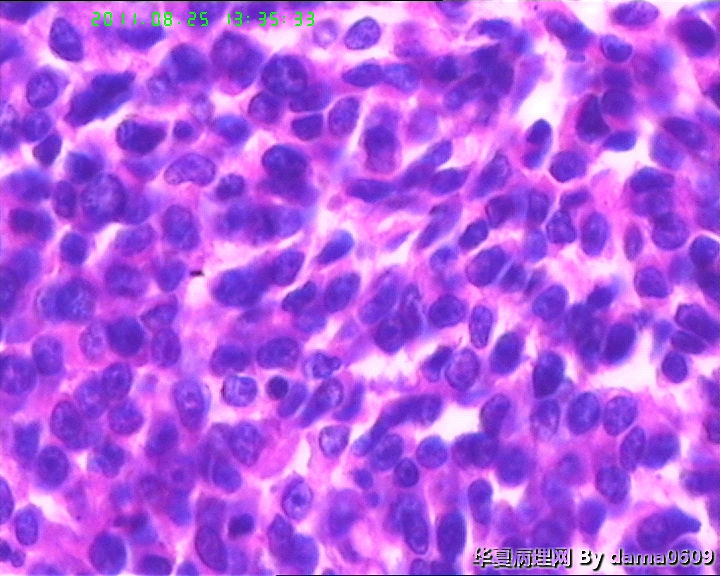

患者男性,39岁。以回盲部肿物行肠镜检查、活检。镜下四块组织内有两块见呈巢状的小细胞(如图

),另两块为粘膜慢性炎表现及坏死组织。学生不知如何分类:未分化癌?类癌?小细胞癌?请老师指教。谢谢!

细胞核较小、深染、一致,核分裂象少见,支持典型类癌。

神经内分泌肿瘤 淋巴瘤 低分化腺癌。。。

下午与腔镜医生沟通过,补充腔镜所见:肿物长满回盲部,大概环肠周,表面黏膜溃疡。患者有右下腹压痛,一直怀疑阑尾炎,余无特殊病史、体征。

又仔细看了一下片子,有核仁,见到核分裂,是否可以定“未分化腺癌”呢?

楼主是想说“未分化癌”?片子切的比较厚,考虑神经内分泌肿瘤,低分化腺癌待排。

神经内分泌肿瘤?低分化腺癌?标一下神经内分泌标记

高级别癌,活检标本,可做IHC先排除高级别神经内分泌肿瘤。

如果神经内分泌阴性,明确分型等手术根治标本。